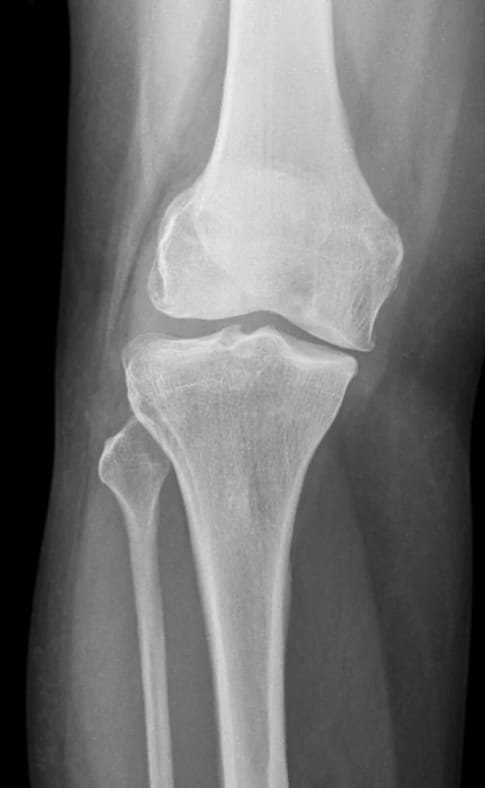

1. O estudo que mudou a ortopedia: Artroscopia

placebo no joelho (Moseley, 2002)

Pacientes com osteoartrite foram divididos em três grupos:

- Artroscopia real com desbridamento

- Artroscopia real com lavagem

- Cirurgia placebo: anestesia, cortes na pele, cheiros, ritual cirúrgico — mas sem colocar

instrumentos dentro da articulação.

1. Artroscopia para Osteoartrite do Joelho

O estudo mais influente sobre a eficácia da artroscopia do joelho em comparação com o placebo é o ensaio controlado e randomizado de Moseley et al. em 2002. Este estudo é frequentemente citado para demonstrar que a cirurgia artroscópica (lavagem ou desbridamento) para osteoartrite não ofereceu benefício superior ao procedimento placebo.

Título do Estudo: A controlled trial of arthroscopic surgery for osteoarthritis of the knee

Autores: J Bruce Moseley et al.

Publicação: N Engl J Med. 2002 Jul 11; 347(2):81-88.

DOI: 10.1056/NEJMoa013259

PMID: 12110735

Observação: Este estudo demonstrou que os resultados após a lavagem artroscópica ou desbridamento artroscópico não foram melhores do que aqueles obtidos após um procedimento placebo em pacientes com osteoartrite do joelho.